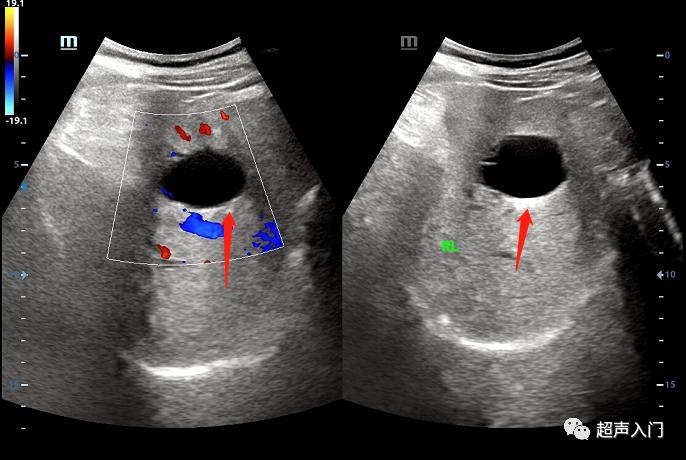

01 肝囊肿

(肝里面那个黑洞洞)

07 胆囊结石

(瞅见那不省心的玩意儿了吗?)

08 胆囊息肉

(胆囊上的肉疙瘩)